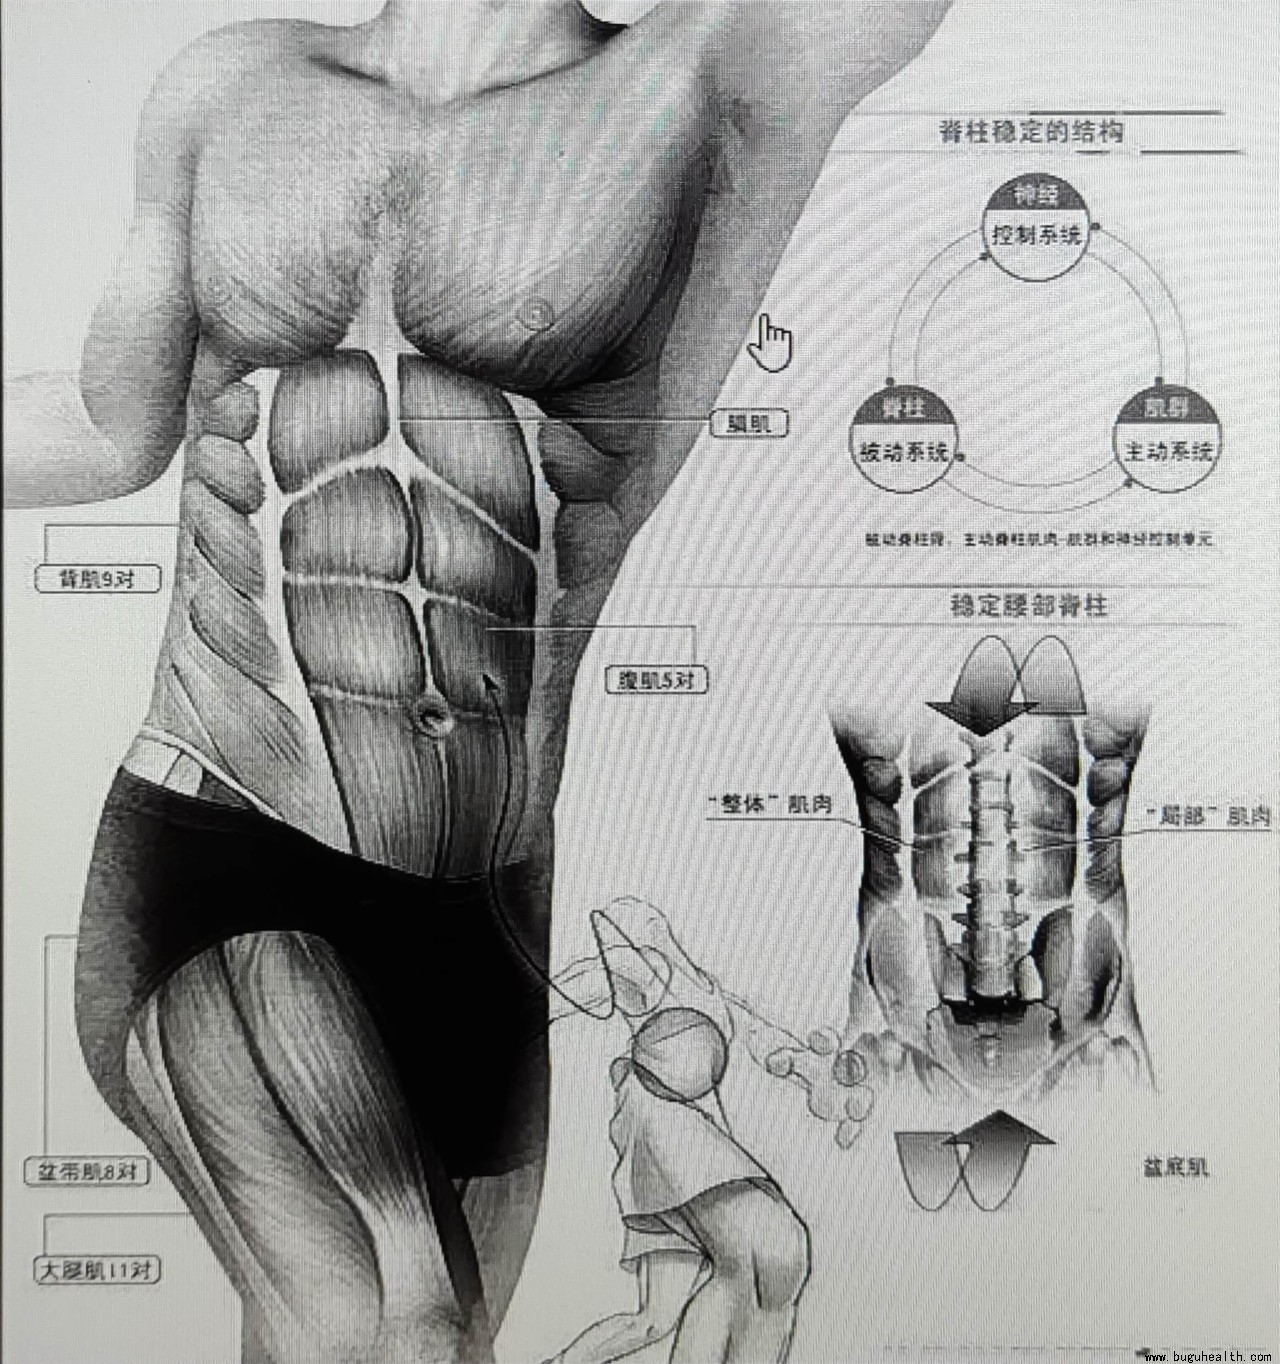

- 布骨医学科普:加强核心,马甲线离你并不遥远 BuGuRMC布骨康复医疗中心 ,2022-09-01

- 我们经常说核心太弱,但我们却没有真正去了解核心是什么?它有什么作用?我们经常说加强核心,但是却不知道如何行动,今天我们就来揭开核心神秘的面纱,和大家一起来学习并了解核心。 .....